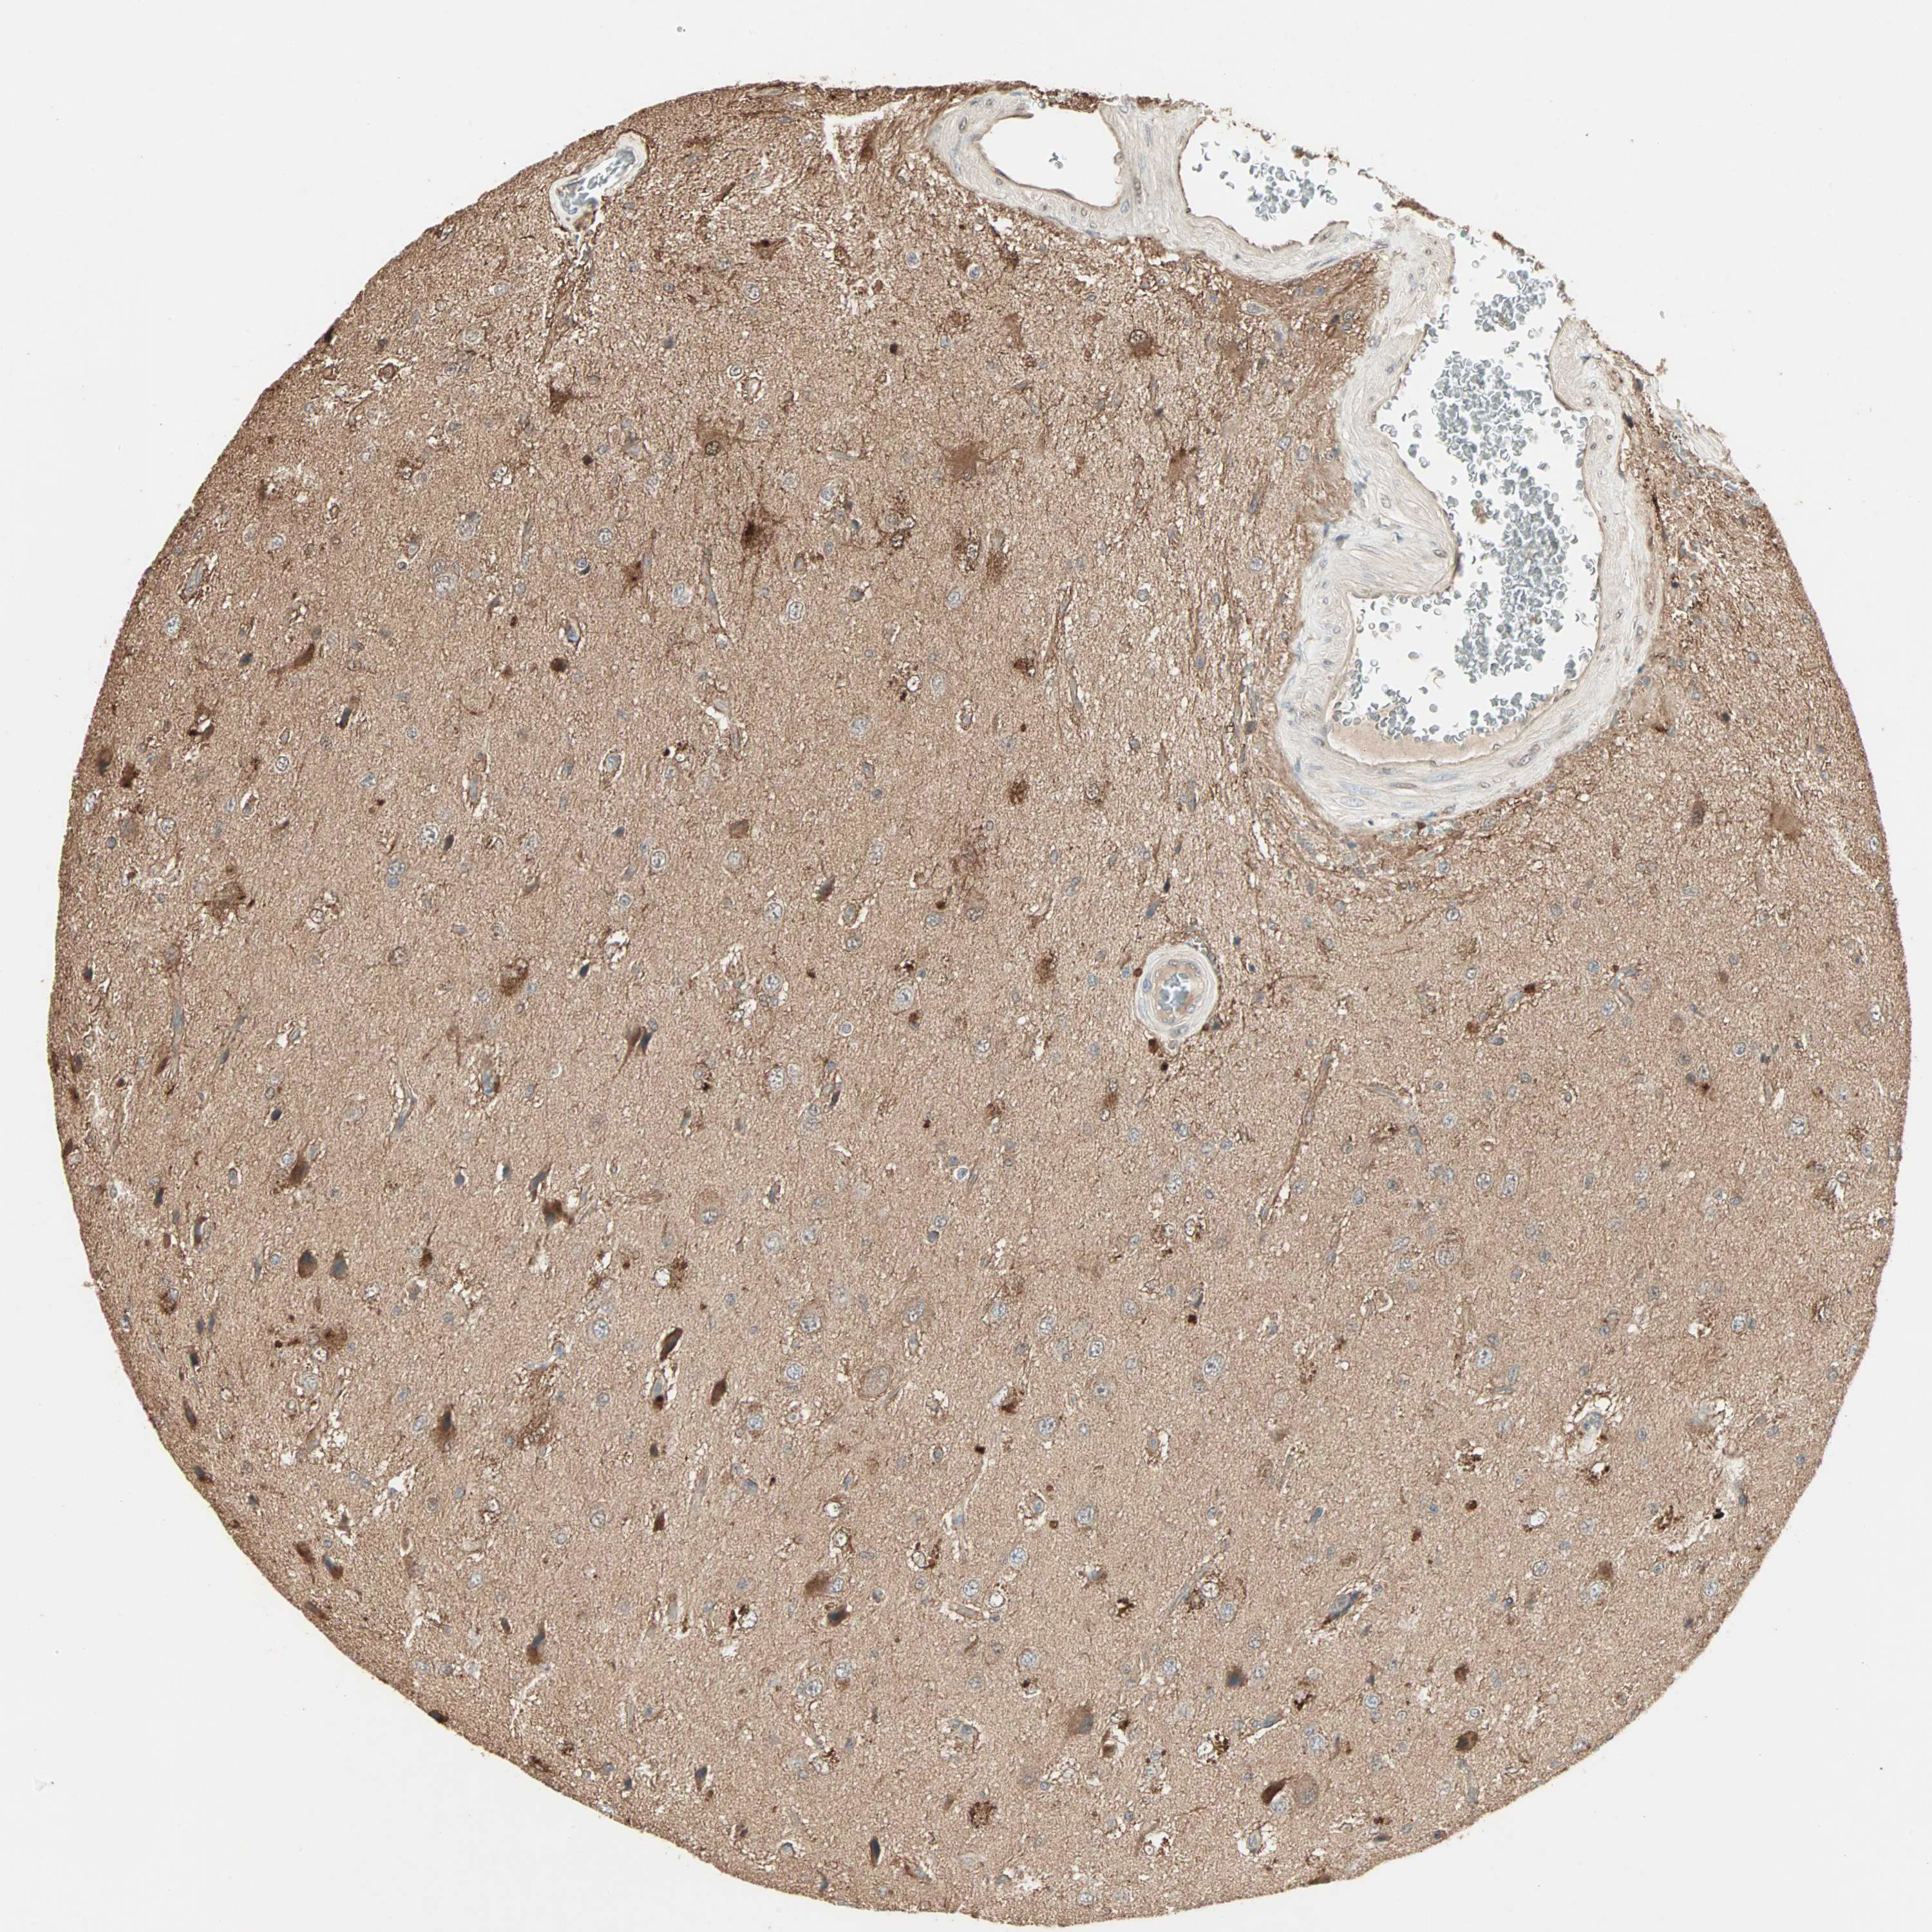

GLIOMA - Protein expressioni

A mouse-over function shows sample information and annotation data. Click on an image to view it in a full screen mode. Samples can be filtered based on level of antibody staining by selecting one or several of the following categories: high, medium, low and not detected. The assay and annotation is described here.

Note that samples used for immunohistochemistry by the Human Protein Atlas do not correspond to samples in the TCGA dataset.

Antibody stainingi

Antibody staining in the annotated cell types in the current human tissue is reported as not detected, low, medium, or high, based on conventional immunohistochemistry profiling in selected tissues. This score is based on the combination of the staining intensity and fraction of stained cells.

Each image is clickable and will lead to virtual microscopy that enables deeper exploration of all samples and also displays staining intensity scores, fraction scores and subcellular localization as well as patient and tissue information for each sample.

Antibody HPA007716

Staining

High

Medium

Low

Not detected

Intensity

Strong

Moderate

Weak

Negative

Quantity

>75%

75%-25%

<25%

None

Location

Nuclear

Cytoplasmic/membranous

Cytoplasmic/membranous,nuclear

Glioma, malignant, Low grade

Glioma, malignant, High grade